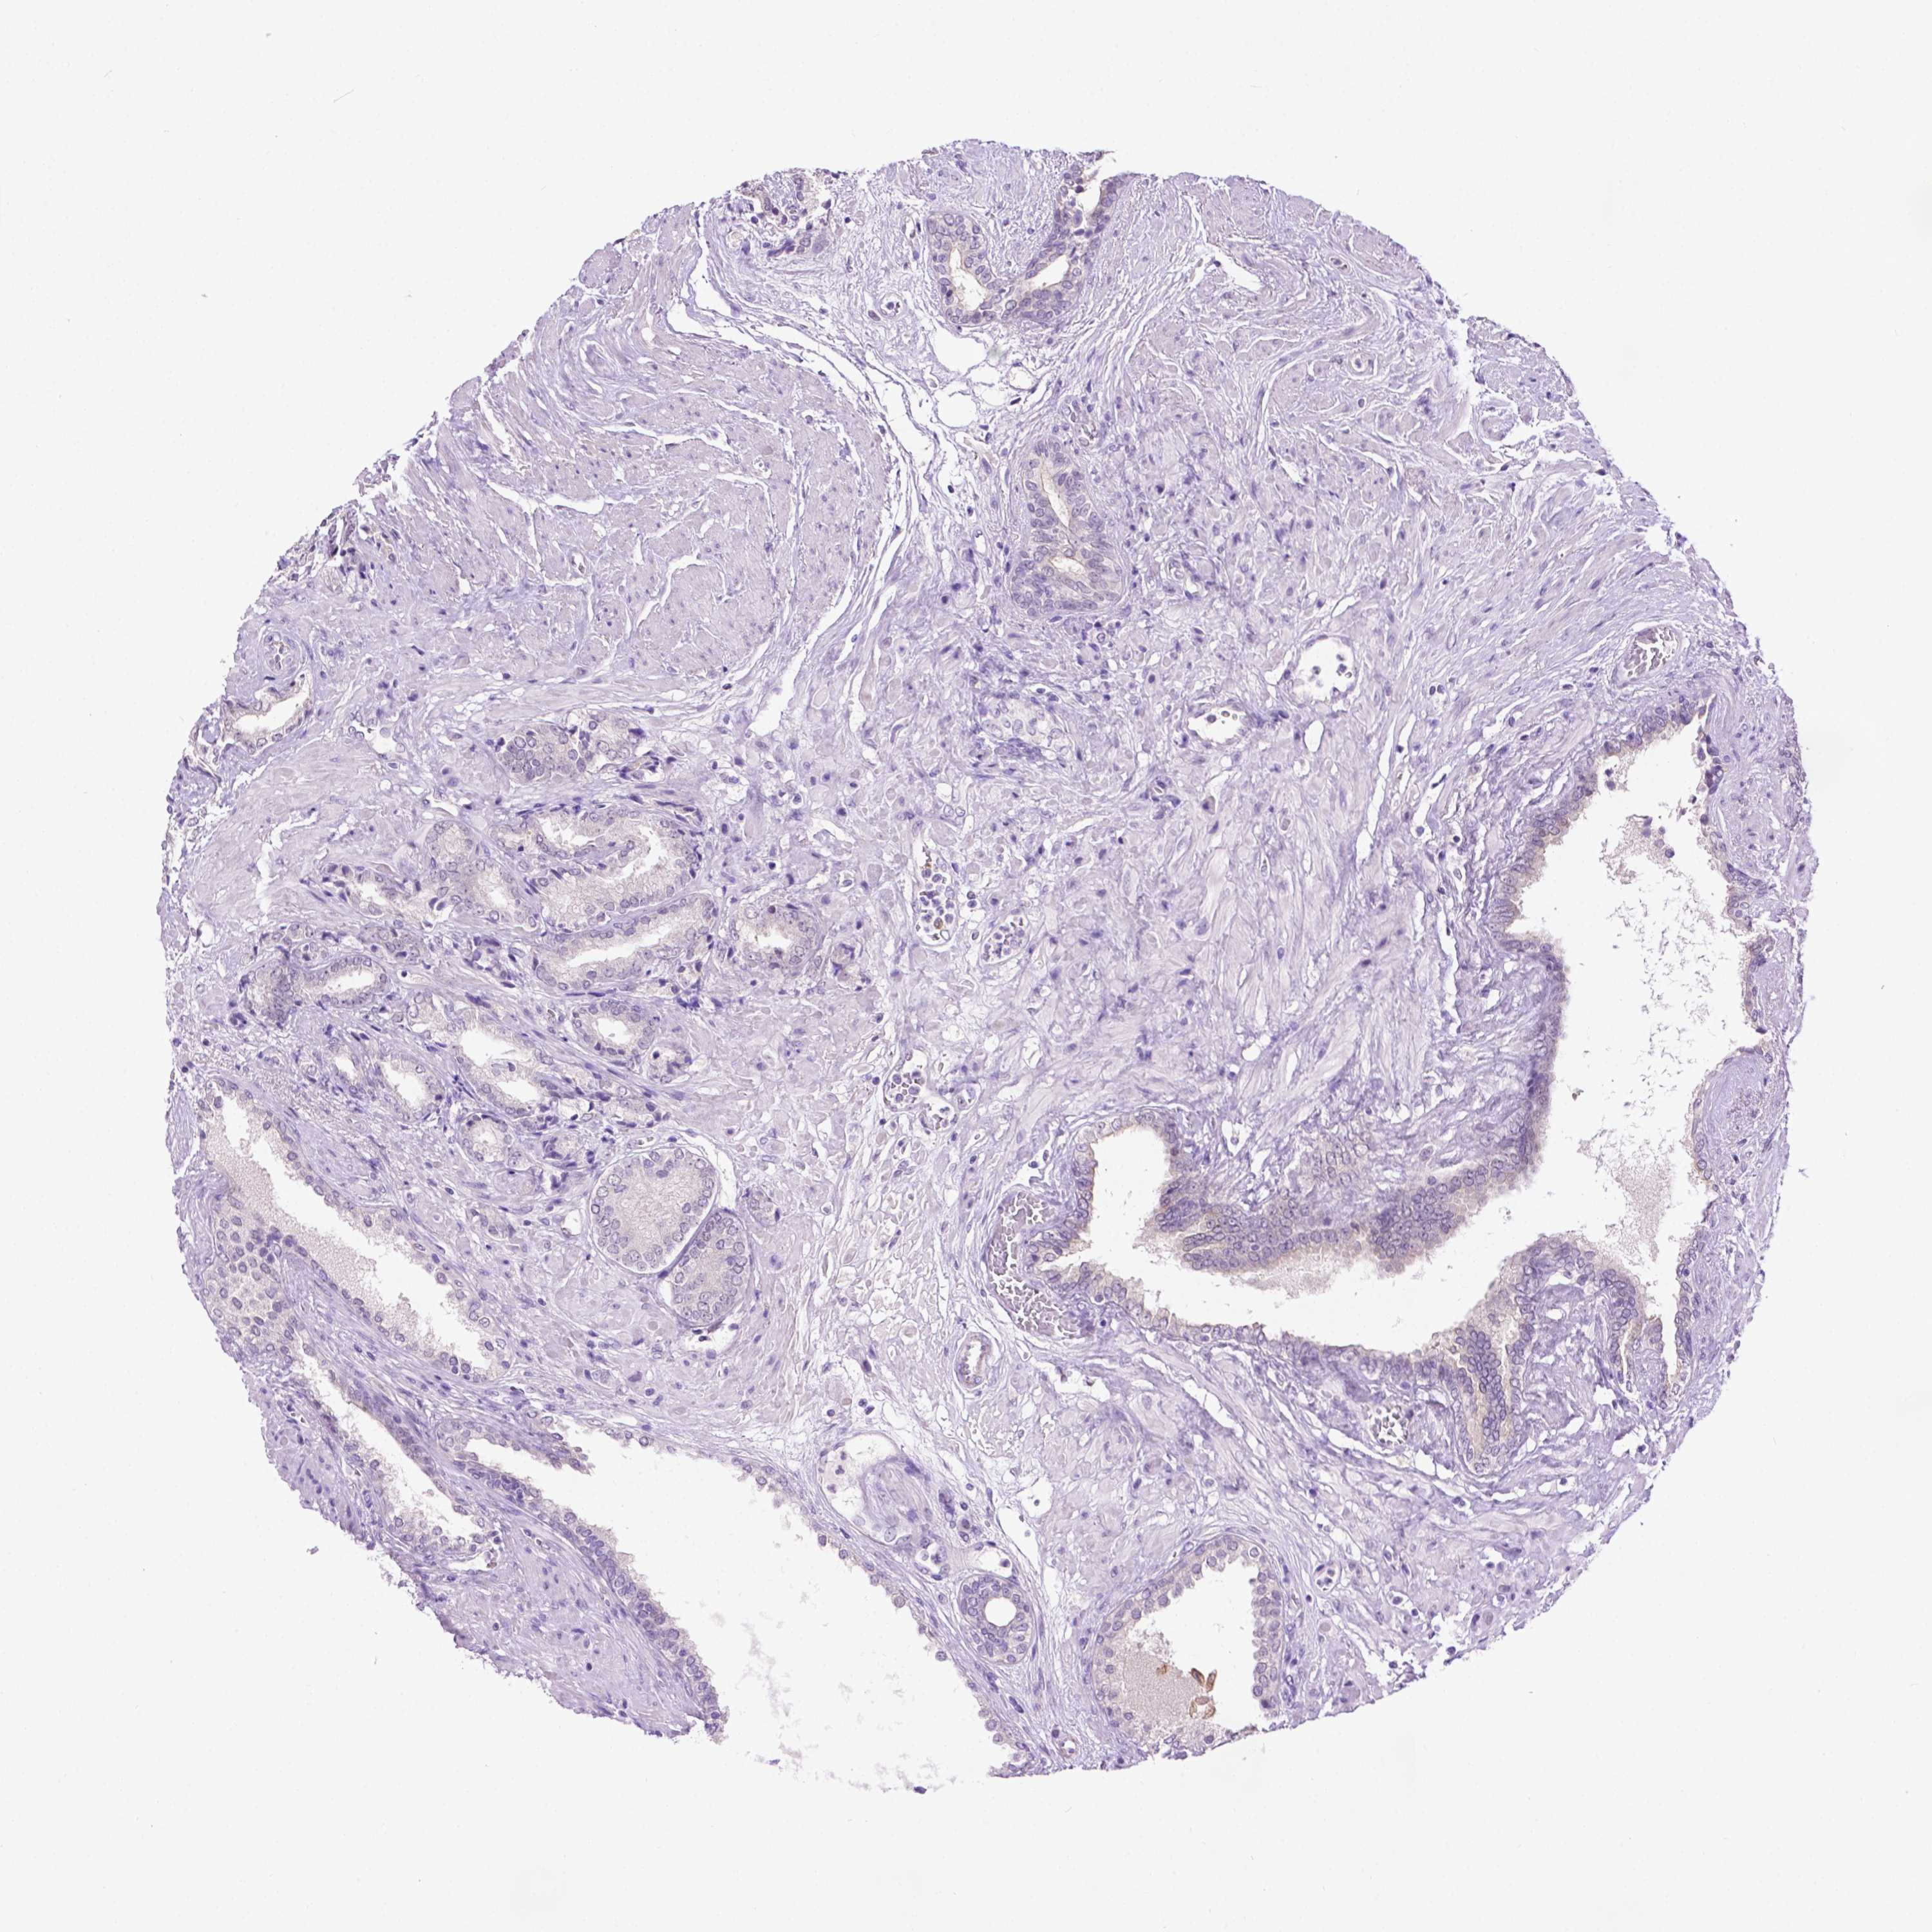

PROSTATE CANCER - Protein expressioni

A mouse-over function shows sample information and annotation data. Click on an image to view it in a full screen mode. Samples can be filtered based on level of antibody staining by selecting one or several of the following categories: high, medium, low and not detected. The assay and annotation is described here.

Note that samples used for immunohistochemistry by the Human Protein Atlas do not correspond to samples in the TCGA dataset.

Antibody stainingi

Antibody staining in the annotated cell types in the current human tissue is reported as not detected, low, medium, or high, based on conventional immunohistochemistry profiling in selected tissues. This score is based on the combination of the staining intensity and fraction of stained cells.

Each image is clickable and will lead to virtual microscopy that enables deeper exploration of all samples and also displays staining intensity scores, fraction scores and subcellular localization as well as patient and tissue information for each sample.

Antibody HPA069097

Staining

High

Medium

Low

Not detected

Intensity

Strong

Moderate

Weak

Negative

Quantity

>75%

75%-25%

<25%

None

Location

Nuclear

Cytoplasmic/membranous

Cytoplasmic/membranous,nuclear

Adenocarcinoma, High grade

Adenocarcinoma, Medium grade

Adenocarcinoma, Low grade